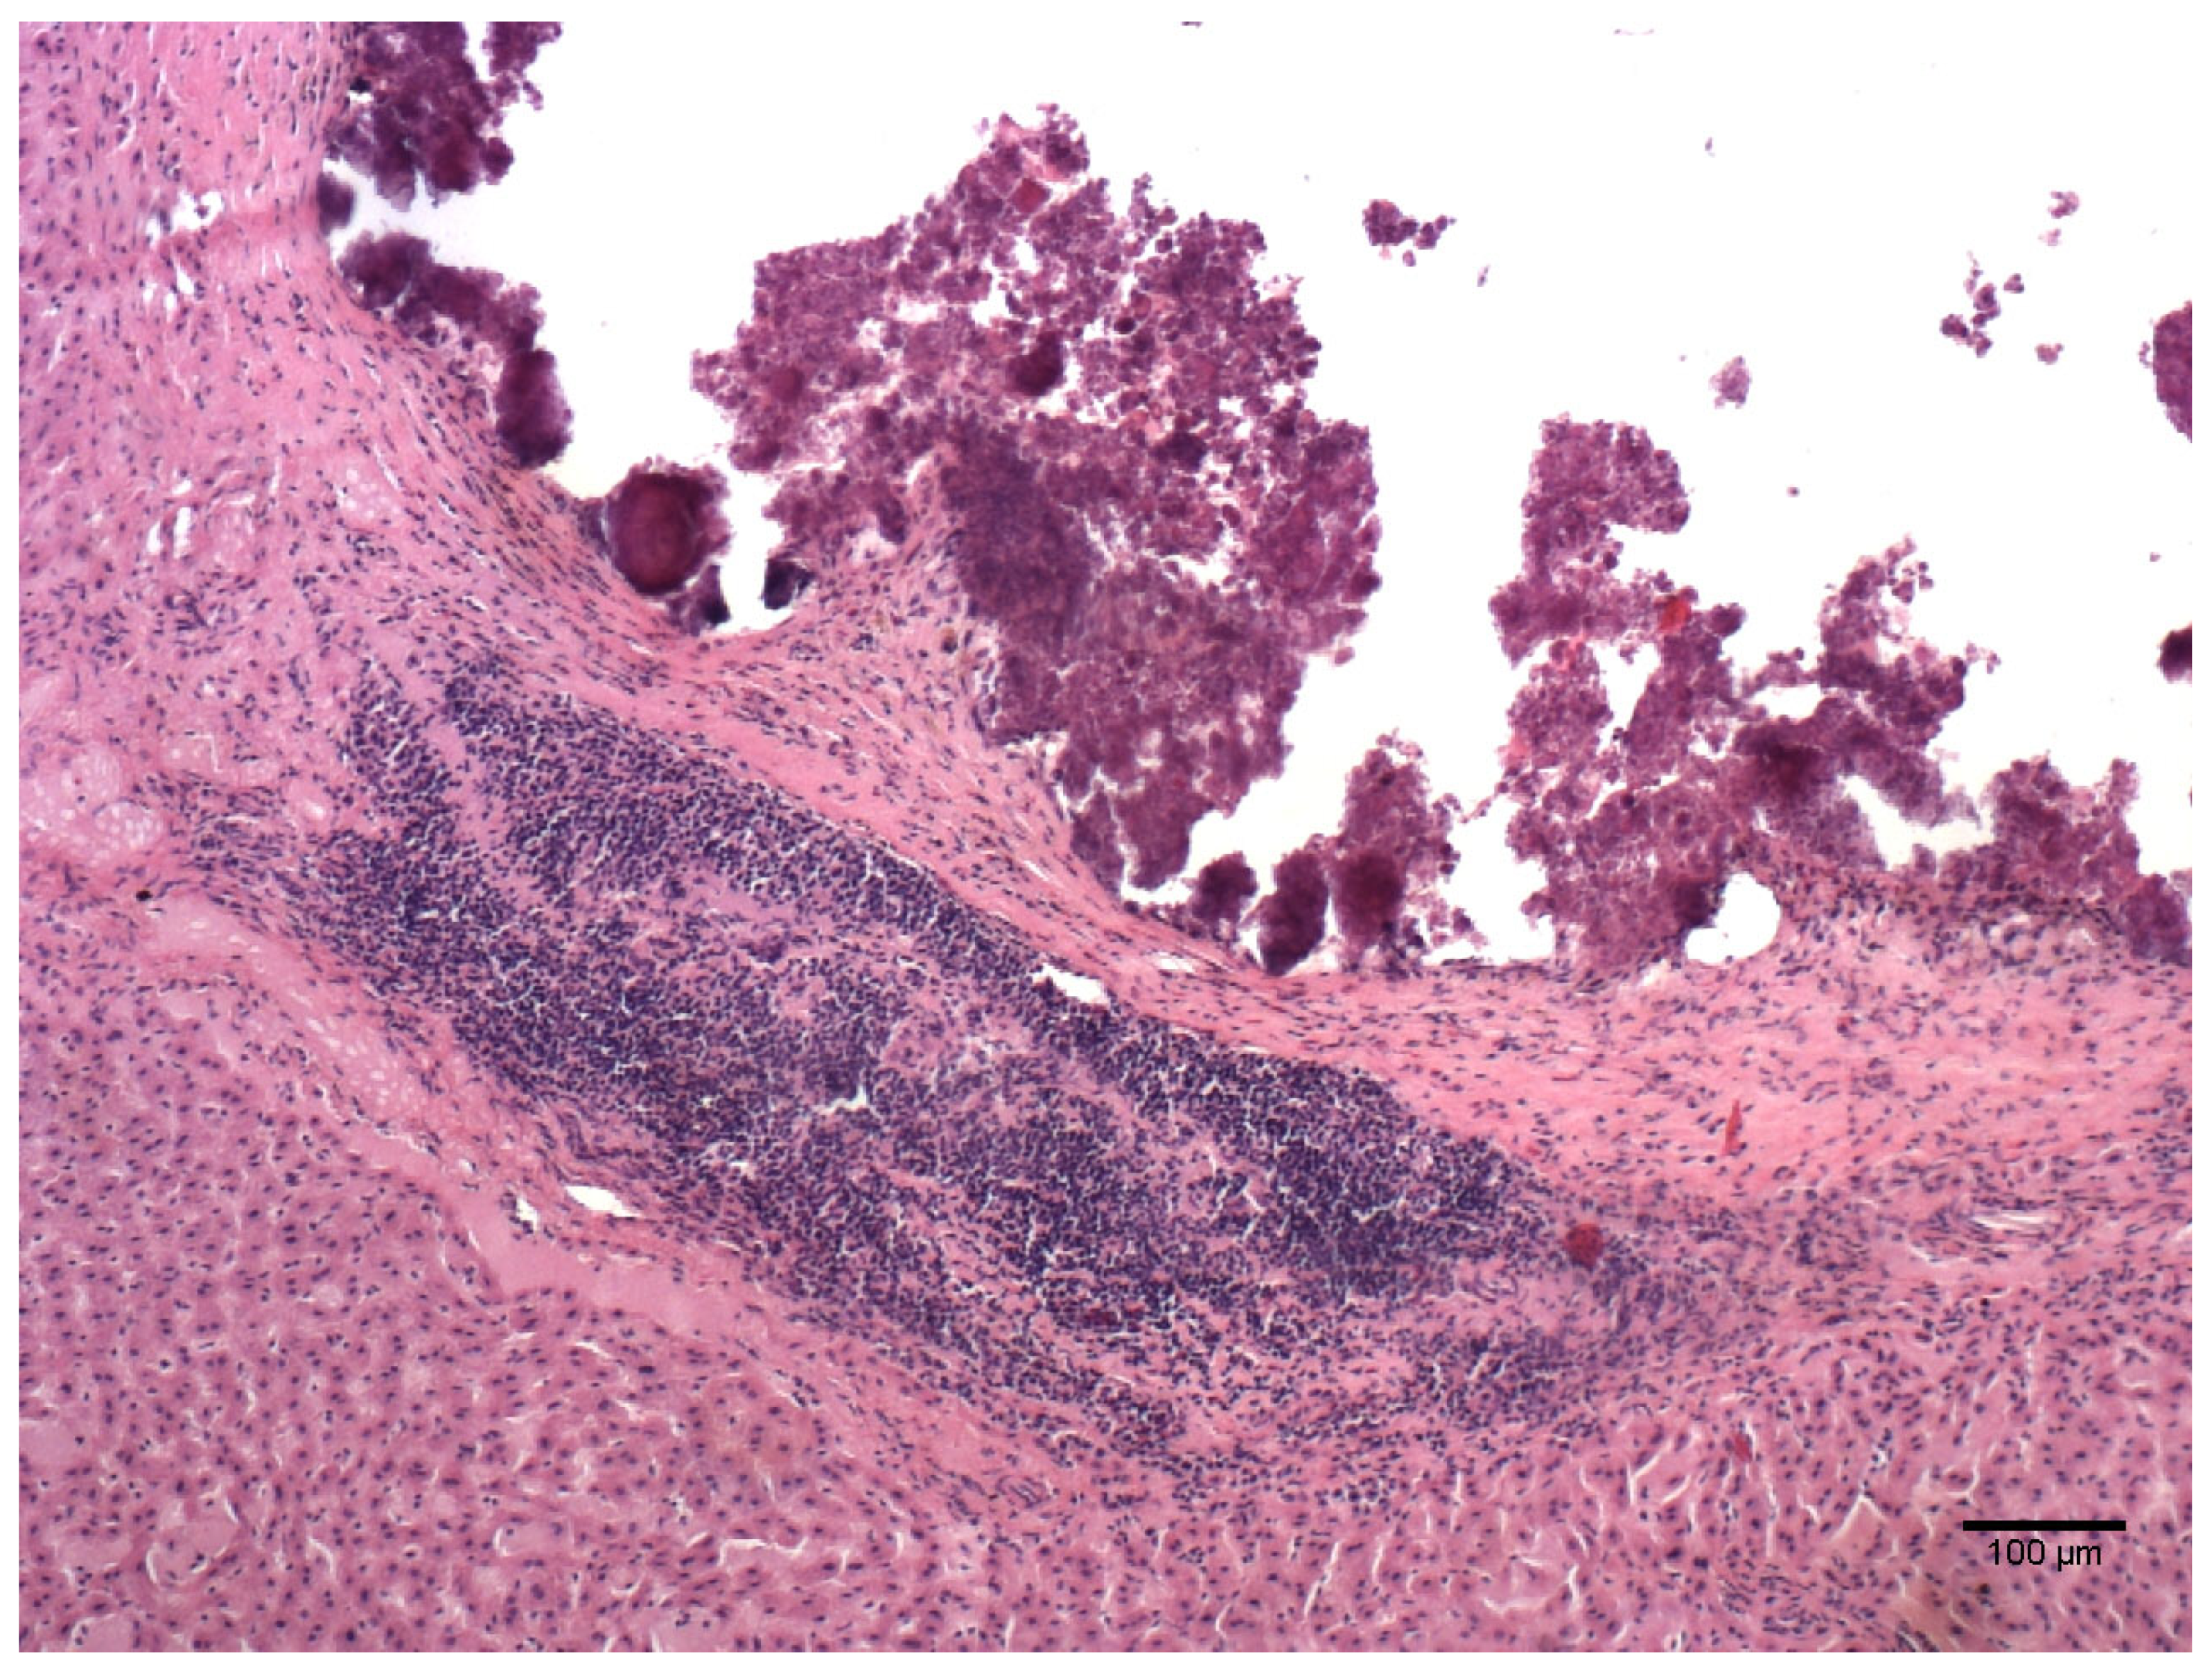

| Lesion | Number of Samples Positive for the Lesion/Total Number of Microscopical Lesions (%) |

|---|---|

| Emphysema | 44/44 (100%) |

| Oedema | 36/44 (81.8%) |

| Parenchymal lymphocytic infiltrate | 36/44 (81.8%) |

| Perivascular lymphocytic infiltrate | 32/44 (72.7%) |

| BALT activation | 27/44 (61.4%) |

| Alveolar thickening | 12/44 (27.3%) |

| Atelectasis | 9/44 (20.5%) |

| Parenchymal lymphocytic and eosinophilic infiltrate | 2/44 (4.5%) |

| Lymphocytic bronchitis | 2/44 (4.5%) |

| Parenchymal neutrophilic infiltrate | 1/44 (2.3%) |

| Focal haemorrhages | 1/44 (2.3%) |